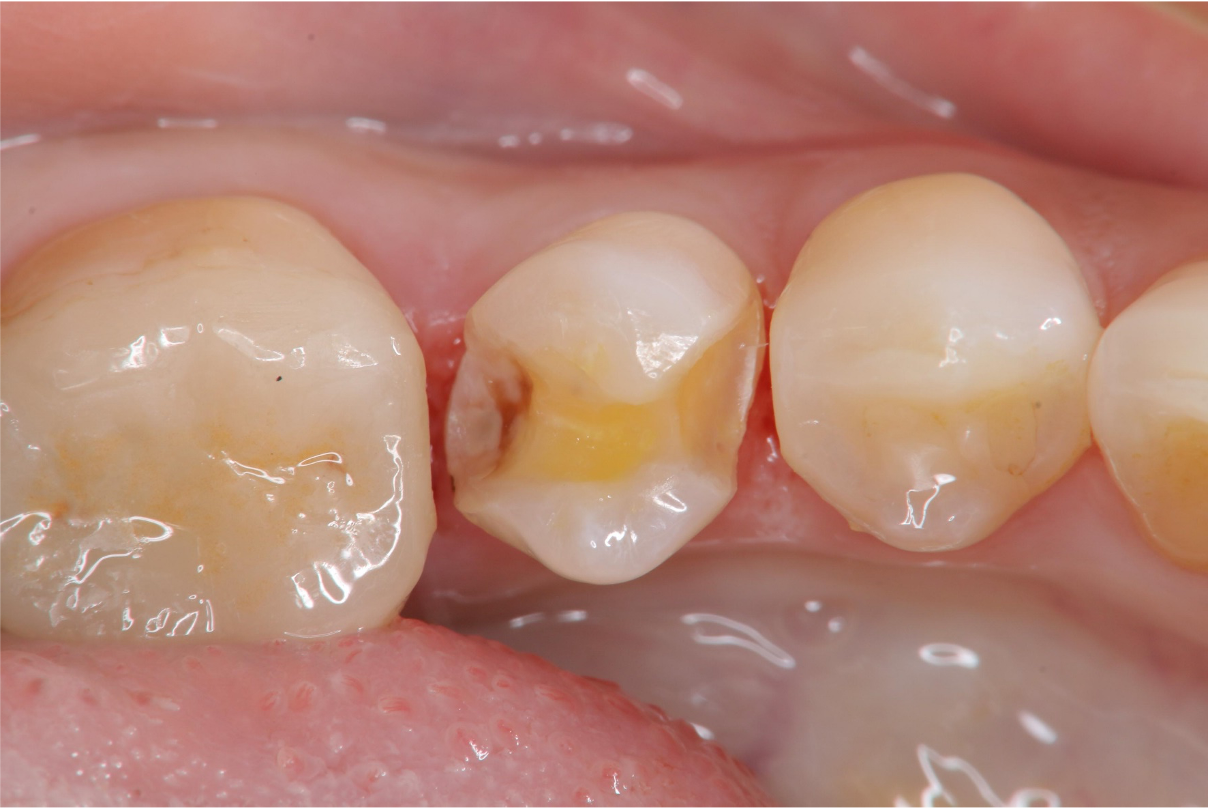

術前、術後比較

陶瓷崁體對於不大的蛀牙,相當有幫助,配合局部複合樹脂復形,更是保留牙齒的好方法。